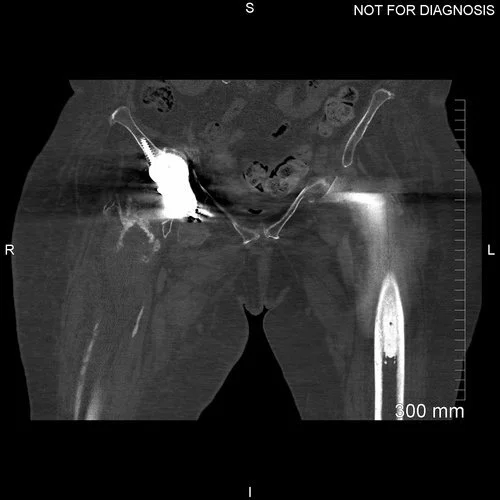

Post-operative CT scan taken two days after the procedure to assess the positioning of the implant.